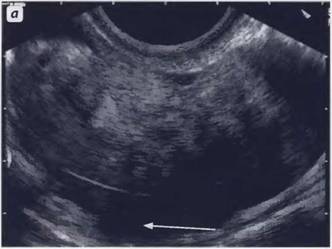

Серозометра причины

Серозометра причины 108 фото